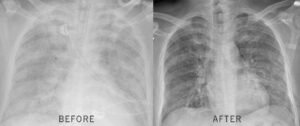

A 73-year-old former stuntman had the same problem. Couldn’t walk to his mailbox without stopping twice, bent over, gasping. His wife found him at 4am turning blue. Within 17 days using this same 30-second valve method, he rode his horse 12 miles without stopping. His lung function jumped 31%.

In a study of 1,847 severe emphysema patients using this valve restoration method: 94% breathed easier within 7 days, 78% threw away their inhalers, and average lung function improved 31% by week 6.